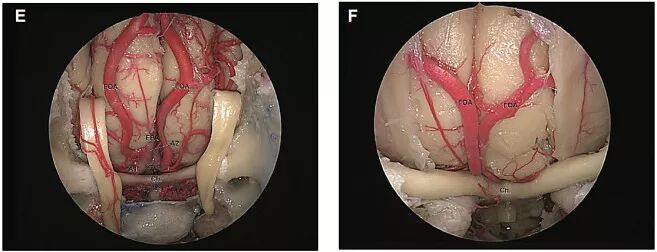

结果显示,20例(80%)标本中前交通动脉位于视交叉后半部分上方,5例位于视交叉前半部分上方(图1)。回返动脉从大脑前动脉A1段发出,在进入前穿质之前分成几个分支,其走行与同侧的ACA-A1段平行。根据RAH与A1段的空间关系分为三种类型:RAH位于A1段前方占40%,位于A1段上方占22%,位于A1段后方占38%。眶额动脉通常从ACA的A2段发出,越过嗅束和直回,达额叶的眶面。嗅束的近端三分之一是FOA越过的最常见部位,其次是中三分之一。额极动脉从ACA的A2段发出,也可与FOA共干起源(图2、3)。作者对RAH、FOA和FPA的直径、三者的起源部位至前交通动脉的距离等解剖关系进行数据统计(表1~3),作为内镜下经鼻入路的解剖学基础。

图3. A.内镜下显示,FOA通常来自ACA的A2段,越过嗅束和直回,到达额叶眶面。嗅束的近端三分之一是与FOA交叉的最常见部位;B.内镜下显示,右侧FOA越过嗅束近端三分之一;C.内镜下显示,FOA进入嗅沟并为其提供血供;D.内镜下显示,右侧FPA与FOA发自同一共干;左侧二者是独立的;E.内镜下显示,另一标本中AcomA复合体和ACA近端分支;双侧FOA未越过直回,而与嗅沟平行。右侧FPA与FOA起源于同一共干,并进入大脑纵裂;F.内镜下显示,在另一样本中,双侧FOA均从ACA的A2段发出,平行于直回走行,到达嗅沟。